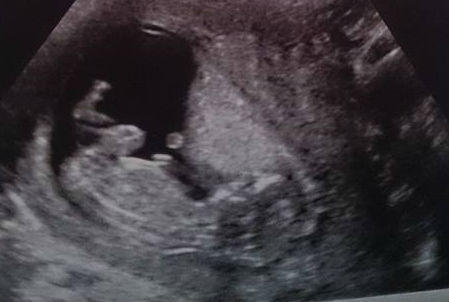

had our scan, it was amazing. due date of 17th september which makes me 13 weeks ish? am sure i heard sonographer mumble something about 'girl' when she was doing measurements etc, but not too clear on what it was. think we're going to have a 4d at about 16 weeks ish :) feel so happy atm, so surreal that theres a baby in there xx

I love seeing all the scan pics :)

Glad all the scans went well today, ours was also good. Baby was very active but in good position so could see very clearly. They confirmed my dd as 15th sept which is the same date my private scan gave. My next scan is the 30th April which seems very soon to me after the long wait for this one.